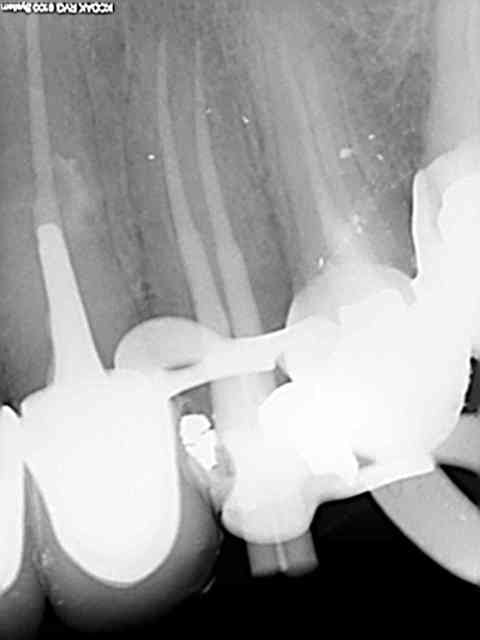

Tout frais de ce matin. T'en veux d'autres ?

R52 kxurpq - Eugenol

R46 plq0yh - Eugenol